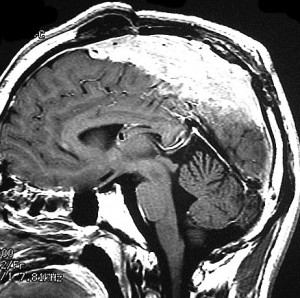

30代の女性に発生した髄膜腫です,一見すると松果体細胞腫と見分けはつきません。右の画像に見られるように典型的な中脳水道狭窄を生じていました。

軽度の閉塞性水頭症もありますが,頭痛も無く無症状なので経過を観察しました。髄膜腫だと診断できるのは,右の画像で見られるようにガレン大静脈が右側に偏っているからです。松果体細胞腫の場合は,ガレン大静脈は上方に変位します。

1年間経過観察したら水頭症が進行して脳室が拡大,腫瘍のサイズも大きくなりました。右側の画像で見られるようにガレン大静脈の左側のテントの下面から発生した髄膜腫でした。

左は手術直後の画像です,手術は左側のテント下面を見るために,後頭部経テント法 OTA occipital transtentorial approach で,小脳テントの左側を切断して腫瘍を全摘出しました。右側は6年後の画像ですが,腫瘍再発はありません。

「注意」症状のない患者さんには,なかなか勧められないリスクの高い手術です。この患者さんの場合は無症状で水頭症も軽度で経過観察をしたのですが,本当はそうしてはならないものでした。閉塞性水頭症が急激に悪化して,急性水頭症のために意識障害になる可能性があるものです。